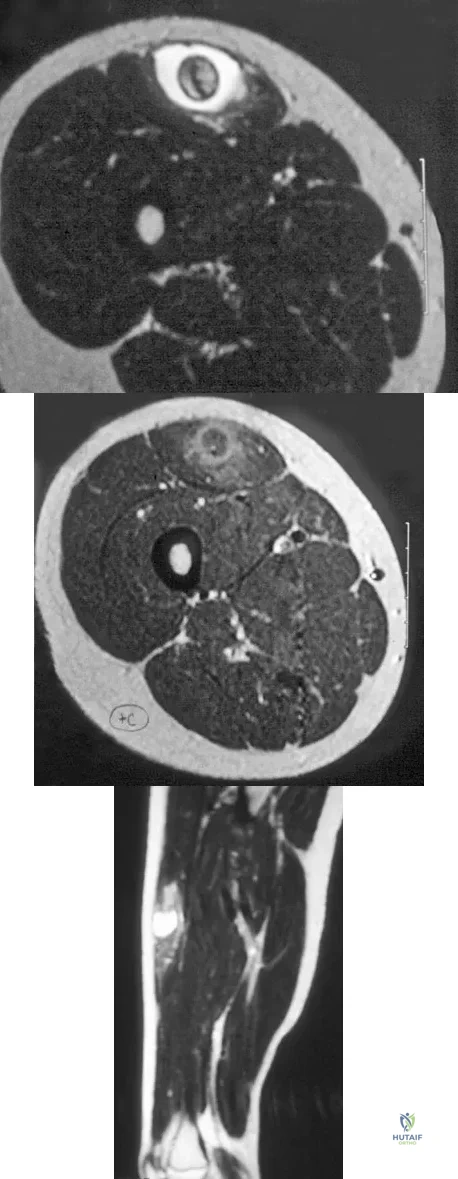

A 40-year-old man reports an enlarging soft-tissue mass in his right shoulder. Based on the MRI scan and biopsy specimens shown in Figures 40a through 40c, what is the most likely diagnosis?